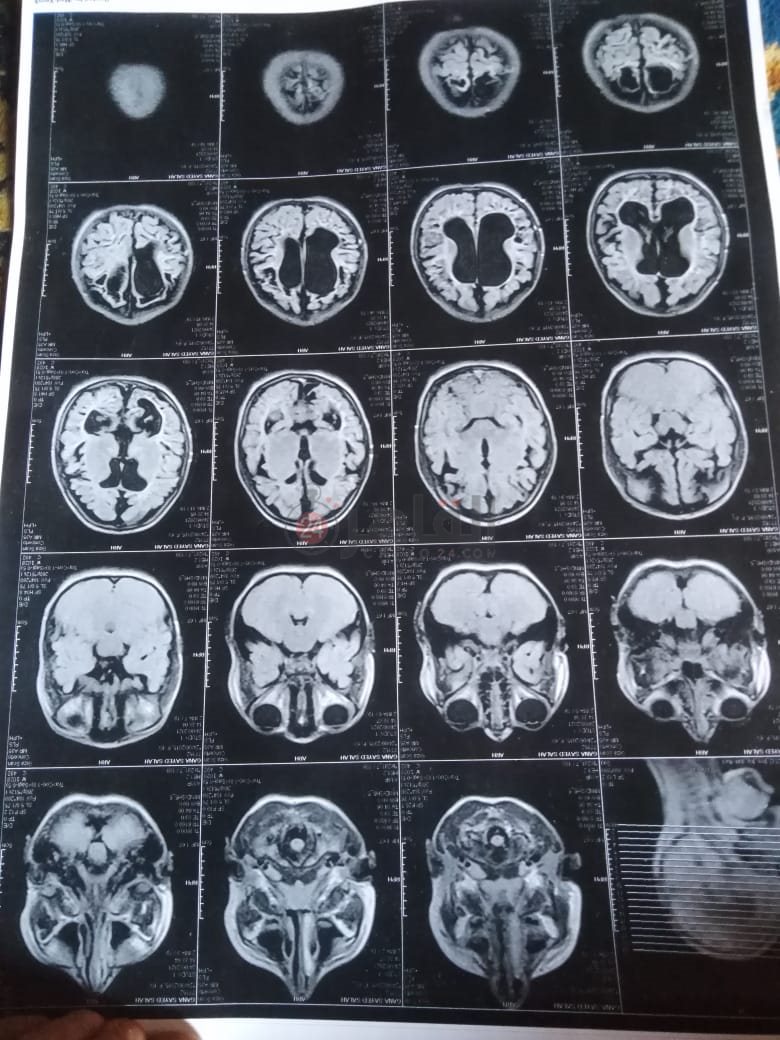

من جانبه، قال صلاح سيد، والد الطفلة جنى صلاح، إن ابنته تعاني من ضمور في المخ منذ ولادتها، نتيجة خطأ طبي، أدى إلى نقص كبير في الأكسجين لديها.

وأضاف في تصريحات خاصة لـ "القاهرة 24": "جنى تبلغ من العمر 6 سنوات، لا تستطيع المشي أو الوقوف على قدميها، نتيجة إصابتها بضمور في المخ منذ ولادتها".

وتابع: "مكنتش بتتحرك خالص، وجسمها طري، روحت كشفت عليها، وعملت أشعة وتحاليل كتير، أتأكدنا إصابتها بضمور في المخ"، مضيفًا:" مش بتعرف تأكل احنا اللي بنأكلها، هي عقلها كويس لكن مش بتتحرك ولا تتكلم".